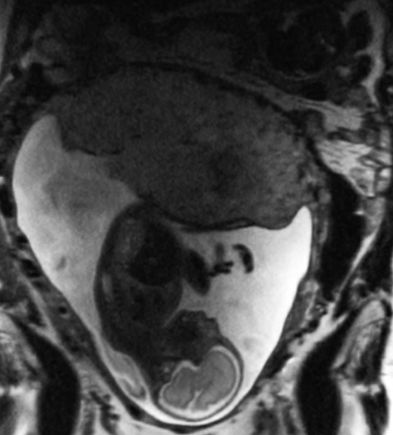

MRI of placenta and baby with the placenta highlighted in red.

A study led by OHSU researchers published in PLOS One demonstrates the potential of quantitative T2* mapping during pregnancy to identify increased risk for adverse obstetric outcome due to placental dysfunction. (OHSU)

The OHSU research team developed and validated an MRI protocol that detects a signal in the blood that is linked to oxygen content. This readout is known as T2*, and T2* values provide key information about oxygen availability and placental blood flow. Oxygen is key for fetal growth and development, so if these values deviate from the normal range, it suggests that something might be wrong. T2* values outside of the normal range could indicate an issue related to the maternal blood supply of oxygen, compromised placental transport or fetal utilization of oxygen.

The study first established a baseline to determine what occurs throughout the course of an uncomplicated pregnancy. Participants underwent three MRI studies during weeks 10 through 40 of pregnancy. Researchers then looked at the ability of MRI to successfully identify complications in pregnancy using the T2* readings produced from the procedures.